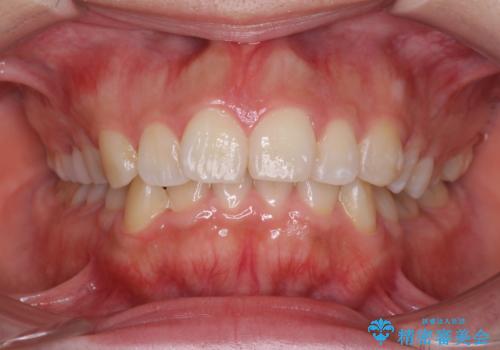

40代女性 前歯の重なり あきらめずに矯正

セラミックと矯正を併用してきれいな前歯へ